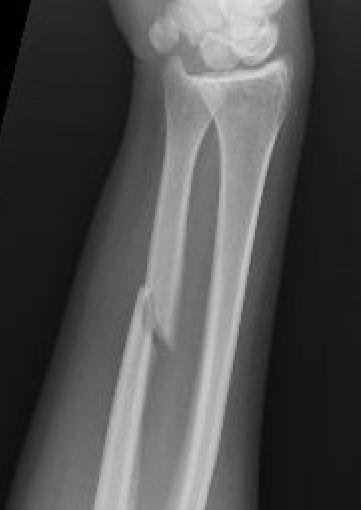

Indications

Acute fractures

- > 50% displacement

- > 10 degrees angulation

- midshaft ulna fractures - higher risk of nonunion